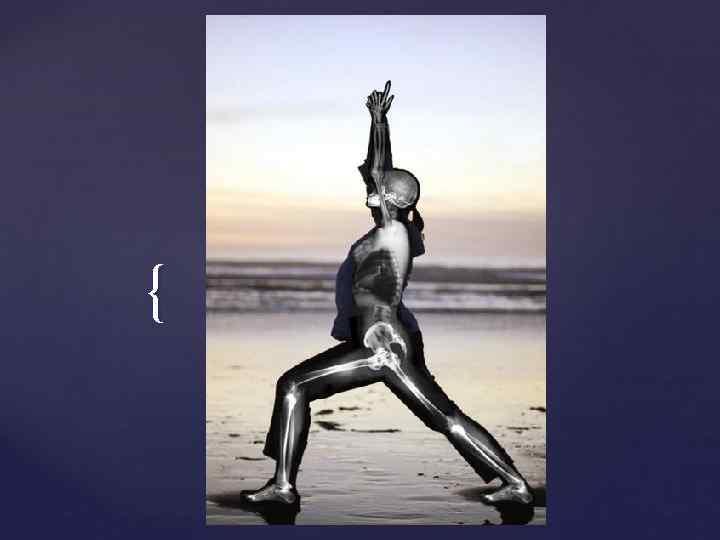

{

{

{

{

{

{